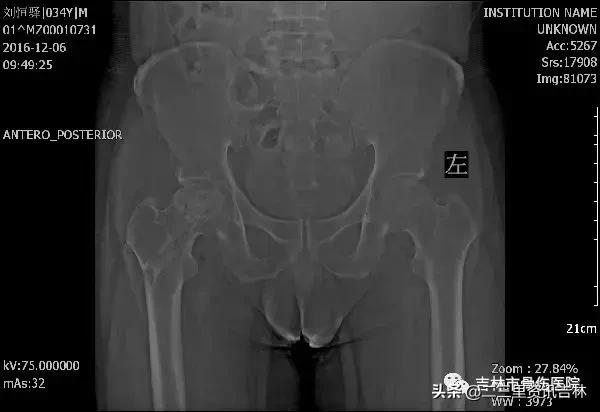

该患于2008年6月因“右股骨颈骨折”在外院行“右侧髋关节置换术”,术后恢复良好,休养至今,于2016年11月30日在自家走路时不慎滑倒摔伤,伤后出现右髋部肿痛,不敢活动,未经处置,在家休养至今未见缓解,现为求系统治疗前来我院就诊,经门诊医生查体拍片后以:“右侧髋关节置换术后假体周围骨折”收入院。

患者入院后给予常规检查,经三级医师查房,临床诊断确诊,查无明显手术禁忌症后在腰硬+全麻麻醉下行“右侧髋关节置换术后假体周围骨折关节翻修术”,术后抗感染、消肿、抗凝、关节功能松动练习等对症治疗,术后患者恢复良好。